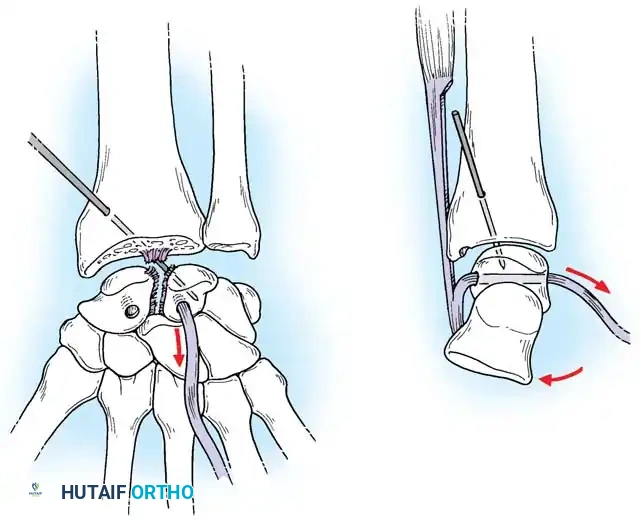

Closed reduction with percutaneous pinning (placing 0.045-inch K-wires from the scaphoid to the capitate and lunate) can be attempted. However, open reduction through a dorsal approach is generally preferred. This allows direct closure of the scapholunate gap, K-wire fixation, and primary repair of the dorsal SL interosseous ligament using suture anchors.